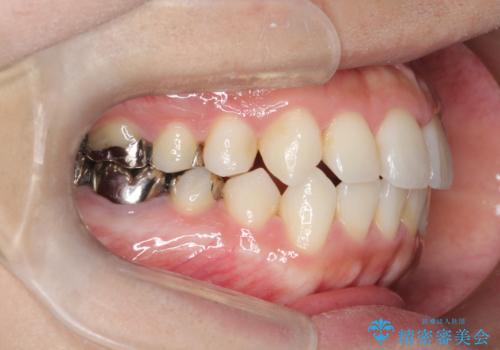

インビザラインで目立たない矯正 ガタガタの歯並びをきれいな歯並びへ

- 全体的なガタガタが気になるとのことで来院されました。

歯と歯のあいだをわずかに削りスペースを作り、ガタガタを改善する計画としました。

装着時間をしっかり守っていただけたのでスムーズに治療をすすめることができました。